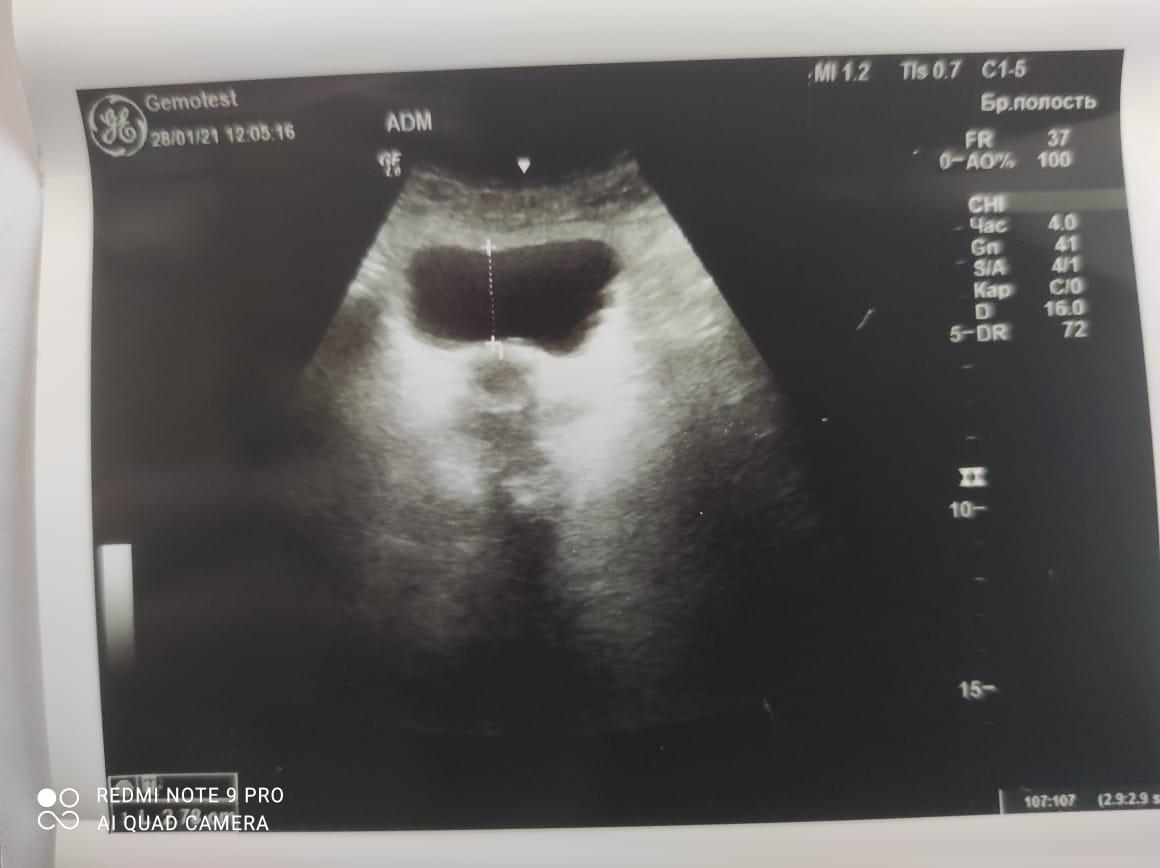

Здравствуйте! При наличии коралловидного камня правой почки(заключение УЗИ), можно предположить причиной боли нарушение уродинамики верхних мочевых путей), что, однако, не подтверждается результатами УЗИ почек( ЧЛС не расширена). Другая, наиболее вероятная возможная причина "боли в боку" - может быть патология опорнодвигательного аппарата. Необходимо проконсультироваться с неврологом и урологом очно, и согласовать возможность применения противовоспалительных, обезболивающих и спазмолитических препаратов - как первый шаг. В дальнейшем необходимо планировать возможное дальнейшее обследование и лечение. Удачи!